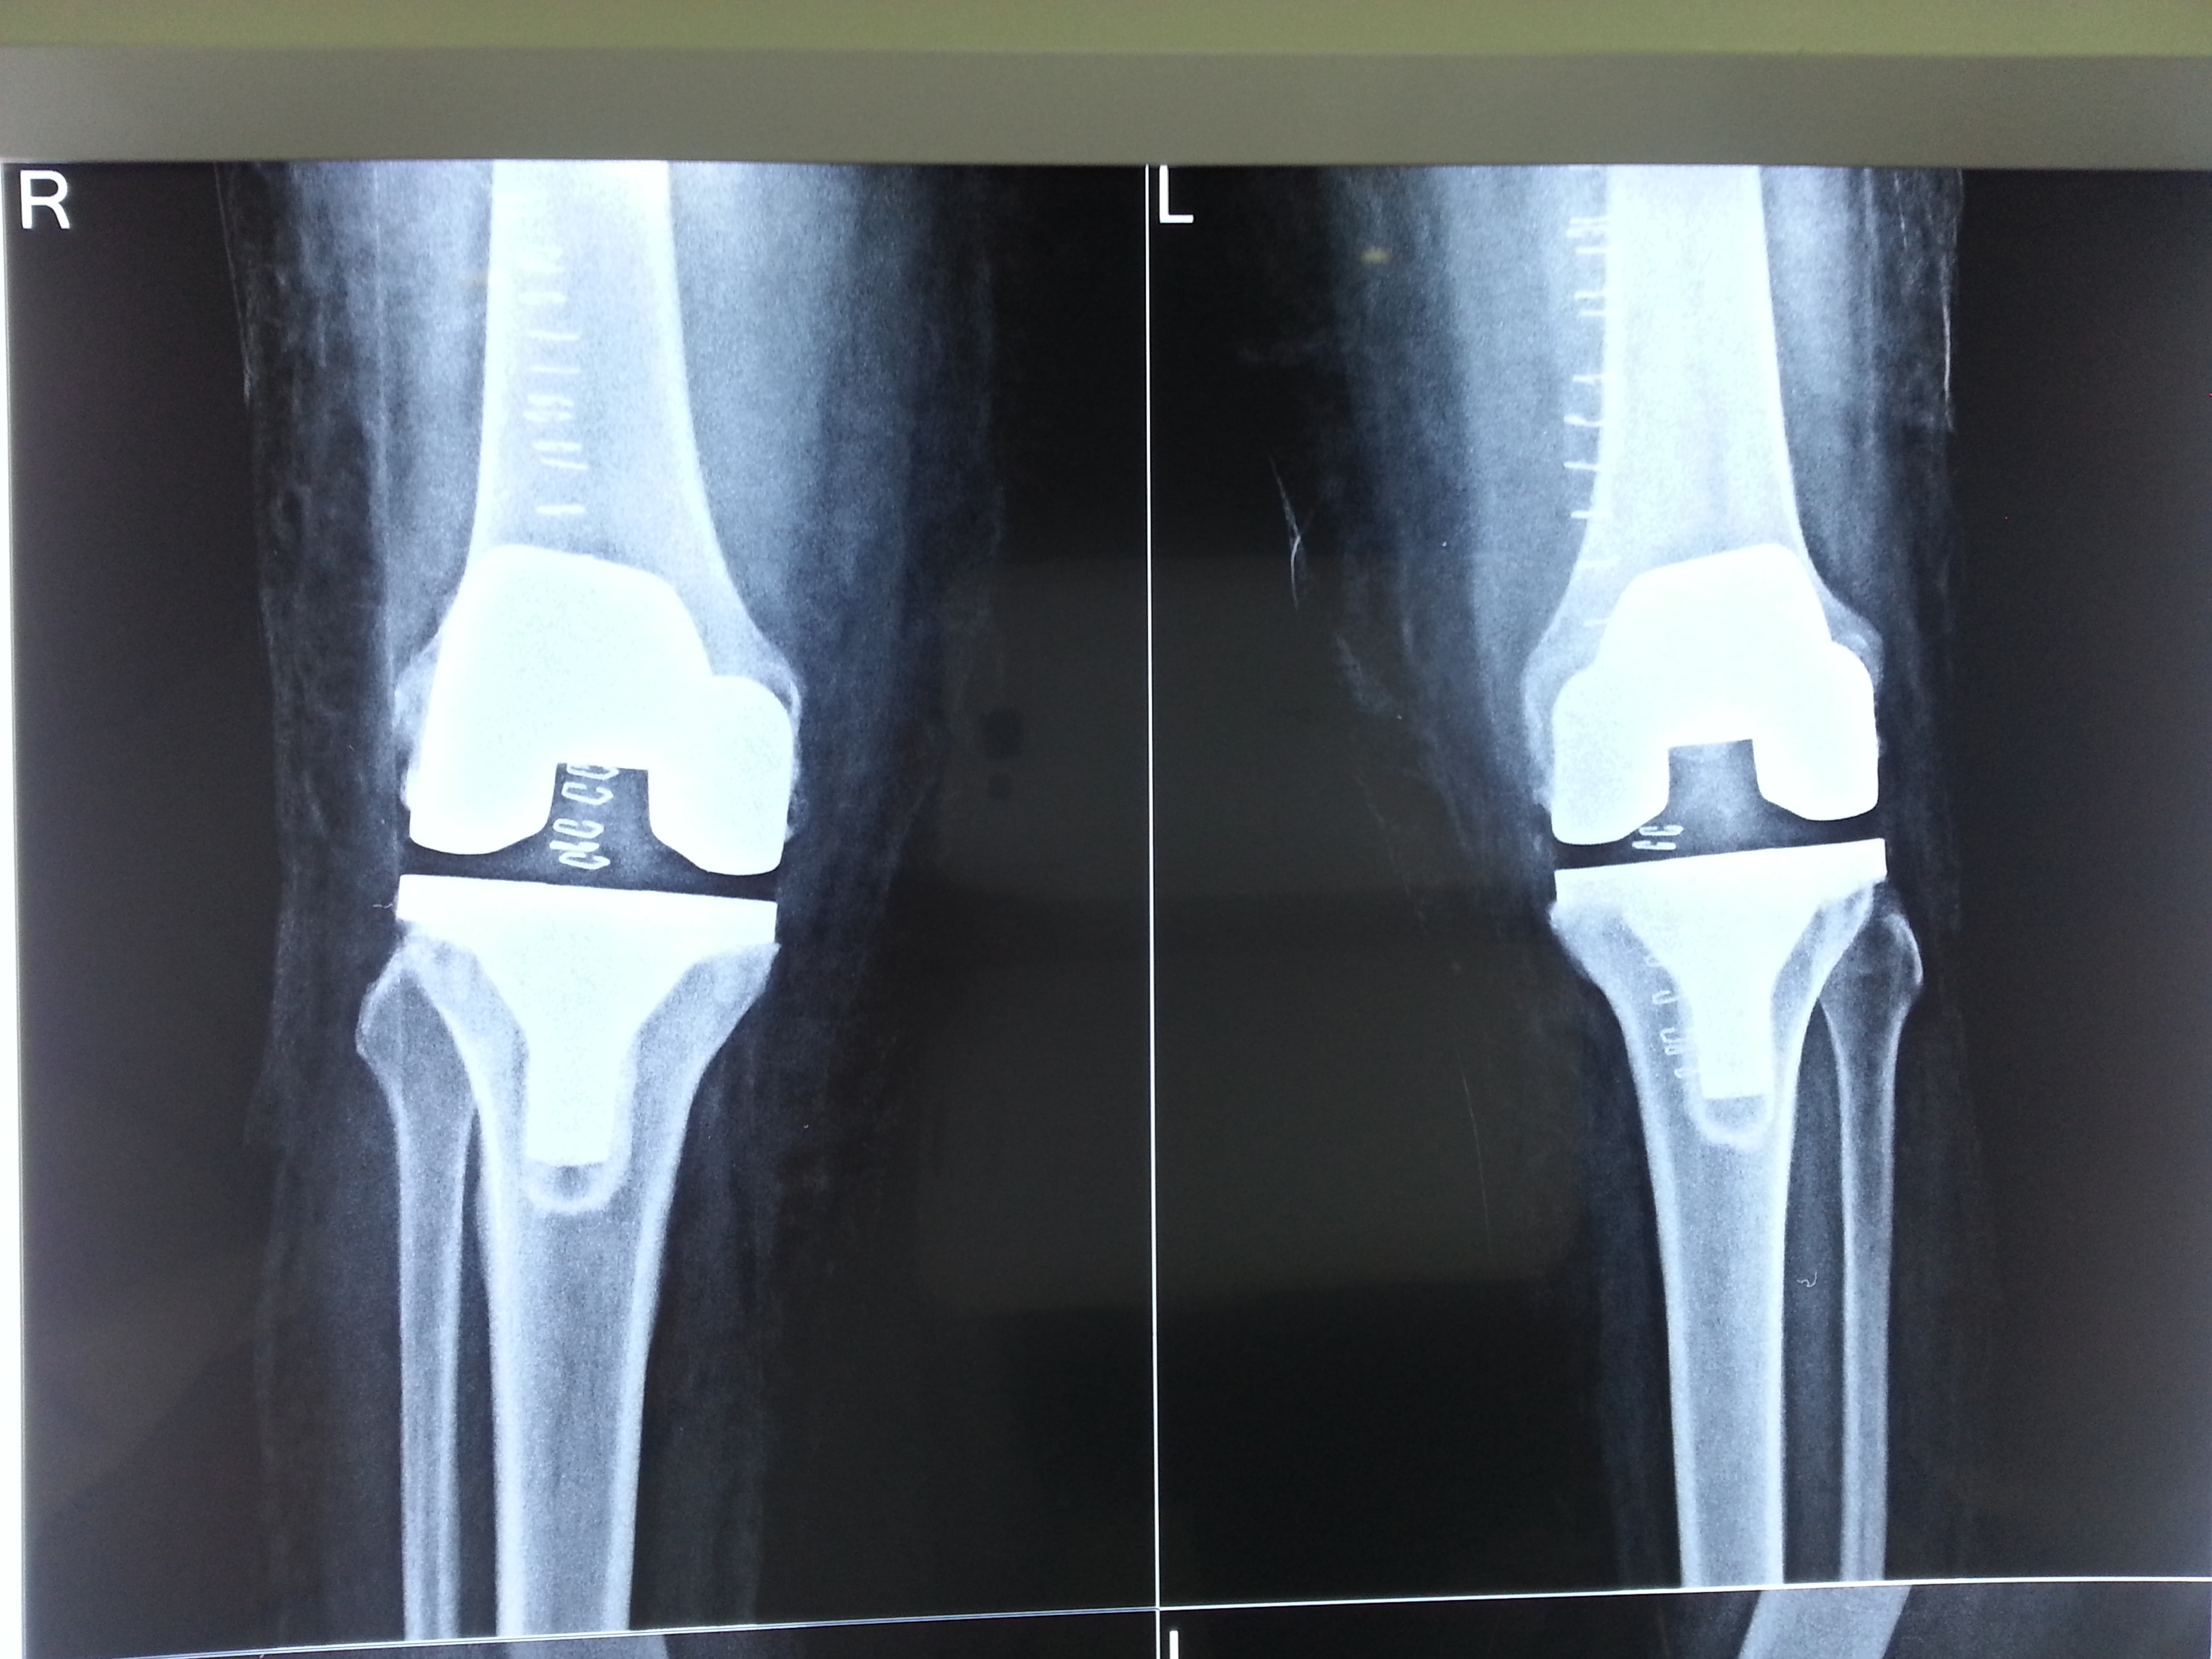

Knee Replacement

Bilateral Knee Pain & Deformity in Both Knees

VarshaBen